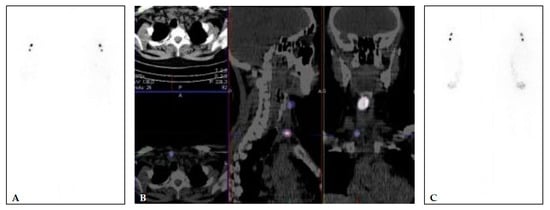

3.3.2. Postoperative Diagnostic Whole-Body Scintigraphy (DxWBS)

- Avram, A.M. Radioiodine Scintigraphy with SPECT/CT: An important diagnostic tool for thyroid cancer staging and risk stratification. J. Nucl. Med. 2012, 53, 754–764. [Google Scholar] [CrossRef] [Green Version]

- Avram, A.M.; Fig, L.M.; Frey, K.A.; Gross, M.D.; Wong, K.K. Preablation 131-I scans with SPECT/CT in postoperative thyroid cancer patients: What is the impact on staging? J. Clin. Endocrinol. Metab. 2013, 98, 1163–1171. [Google Scholar] [CrossRef] [Green Version]

- Avram, A.M.; Esfandiari, N.H.; Wong, K.K. Preablation 131-I scans with SPECT/CT contribute to thyroid cancer risk stratification and 131-I therapy planning. J. Clin. Endocrinol. Metab. 2015, 100, 1895–1902. [Google Scholar] [CrossRef] [PubMed]